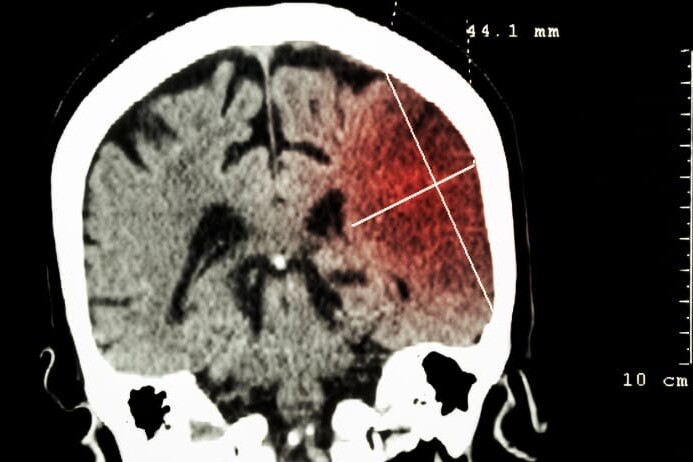

1. Emergency Diagnosis and Stabilization

- Neurological assessment as soon as symptoms appear

- Urgent CT/MRI brain scans to identify stroke type

- Clot-busting therapy (tPA) for ischemic stroke

- Emergency intervention for hemorrhagic stroke

- ICU admission for stabilization if required